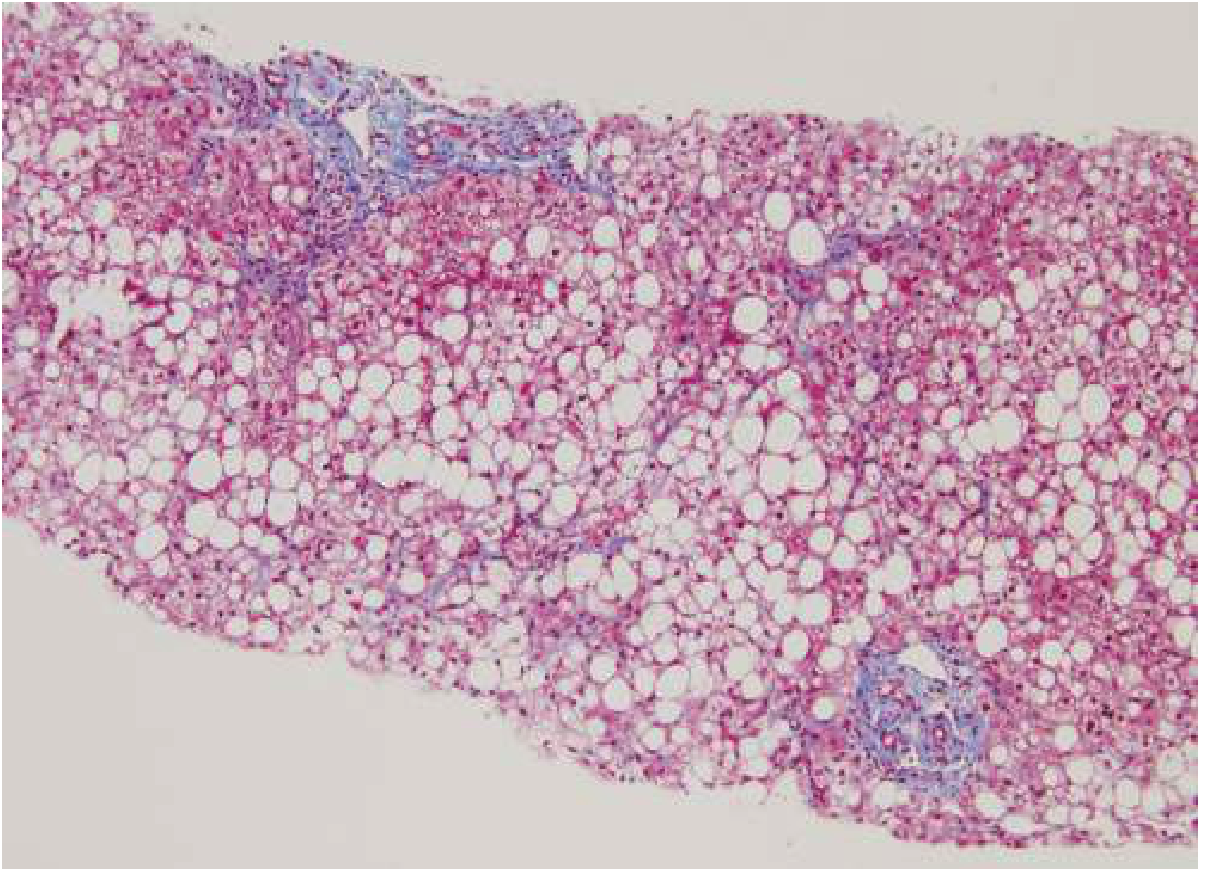

Liver Biopsy NASH

Liver biopsy showing NASH: the large white circles are fat droplets inside hepatocytes, with early fibrosis (blue areas). — Goldman-Cecil Medicine